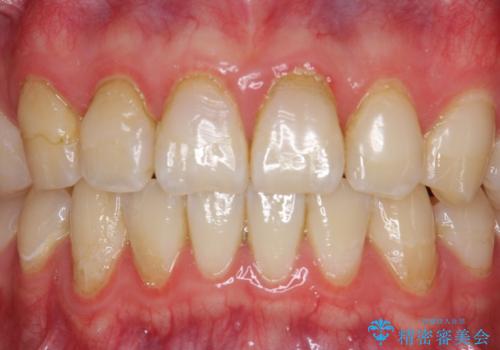

- 右上2、3番目の歯の色・形が気になるといらっしゃった方の症例です。

古い樹脂を除去後、オールセラミッククラウンによる補綴を行いました。

今回用いたオールセラミッククラウンは、ジルコニアフレームという白い素材の上にセラミックを盛っているため審美性が非常に高いのが特徴です。

またジルコニアは人工ダイヤモンドの材料にも使われているほど高い強度を持っており、そのためオールセラミッククラウンは審美性だけでなく、奥歯やブリッジの補綴も可能とするクラウンです。